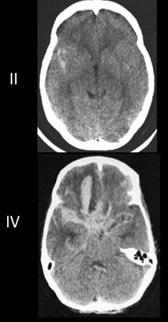

Las escalas para clasificar la severidad de la HSA tanto clínica como radiológicamente son las escalas de Hunt - Hess y la escala de Fisher respectivamente.

Escala de Fisher

Grado Descripción

I Sin evidencia de sangrado en cisternas ni ventrículos

II Sangre difusa fina, con una capa <1 mm en cisternas medida verticalmente

III Coágulo grueso cisternal, >1 mm en cisternas medido verticalmente

IV Hematoma intraparenquimatoso, hemorragia intraventricular, +/- sangrado difuso.

Figura 6. TAC: Hemorragia subaracnoidea (HSA) (Escala de Fisher)